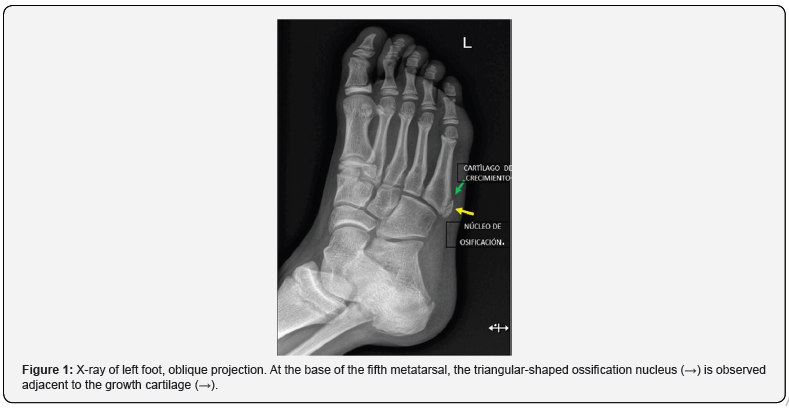

Regarding the anatomy of the fifth metatarsal in the pediatric population, we must remember the appearance of secondary ossification centers that the metatarsals and phalanges have and can be confused with injuries, the rest of the bones are formed from a primary center; The primary one occurs from the eighth month of life and the secondary one is different in each metatarsal (Figure 1) [3]. The importance of the styloid process of the fifth metatarsal in the insertion of the tendon of the peroneus brevis muscle and the lateral cord of the plantar aponeurosis, important in the joint stability of the ankle [4]. The ossification centers begin to appear between 2 months and 2 years and fuse between 13 and 22 years, while the basal styloid process develops between 9 and 11 years in girls and between 11 and 14 years in children, merging two or three years later (Figure 2) [5].